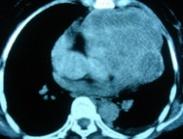

據國內外文獻資料:心包內惡性畸胎瘤是心包內畸胎瘤的一種特殊病理形態。惡性程度較高,早期易侵犯心室、心房及升主動脈等處,引起一系列生理及病理性改變。

- 常見癥狀:心律失常、心絞痛、心動過速、心包積液、胸痛、胸部刺痛、心前區不適感